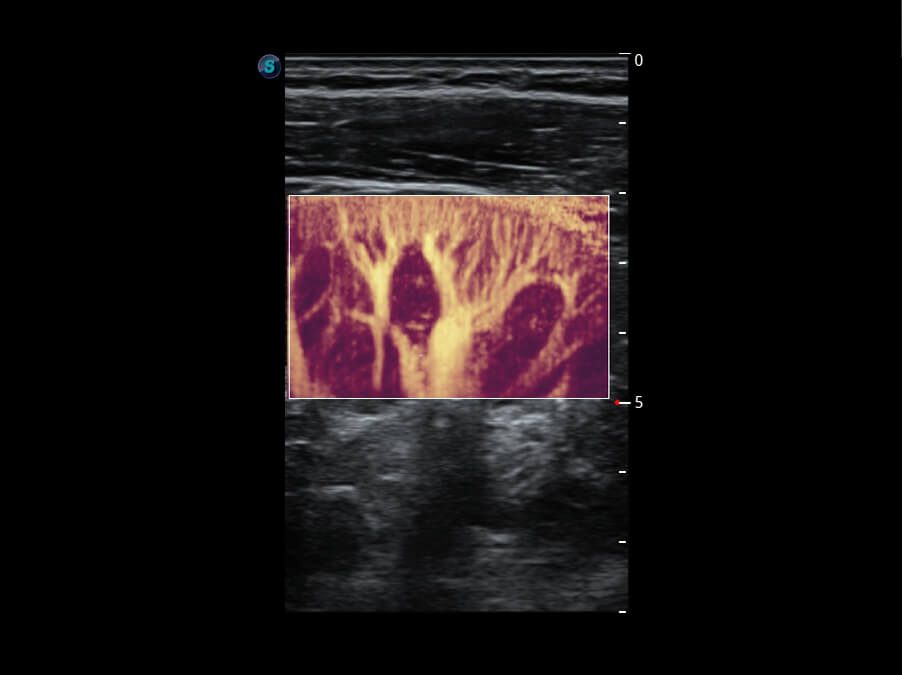

S60创新的探头工艺、高精度模数转换系统、前沿的波束重建技术,从前端信号处理每一个环节采集无损声学数据,真实还原组织原貌,再现解剖细节。

创新的超宽频带技术,为容积成像带来优质的二维图像基础,为您呈现更丰富的结构细节,栩栩如生地展示宝宝的宫内形态以及各种组织的立体结构。